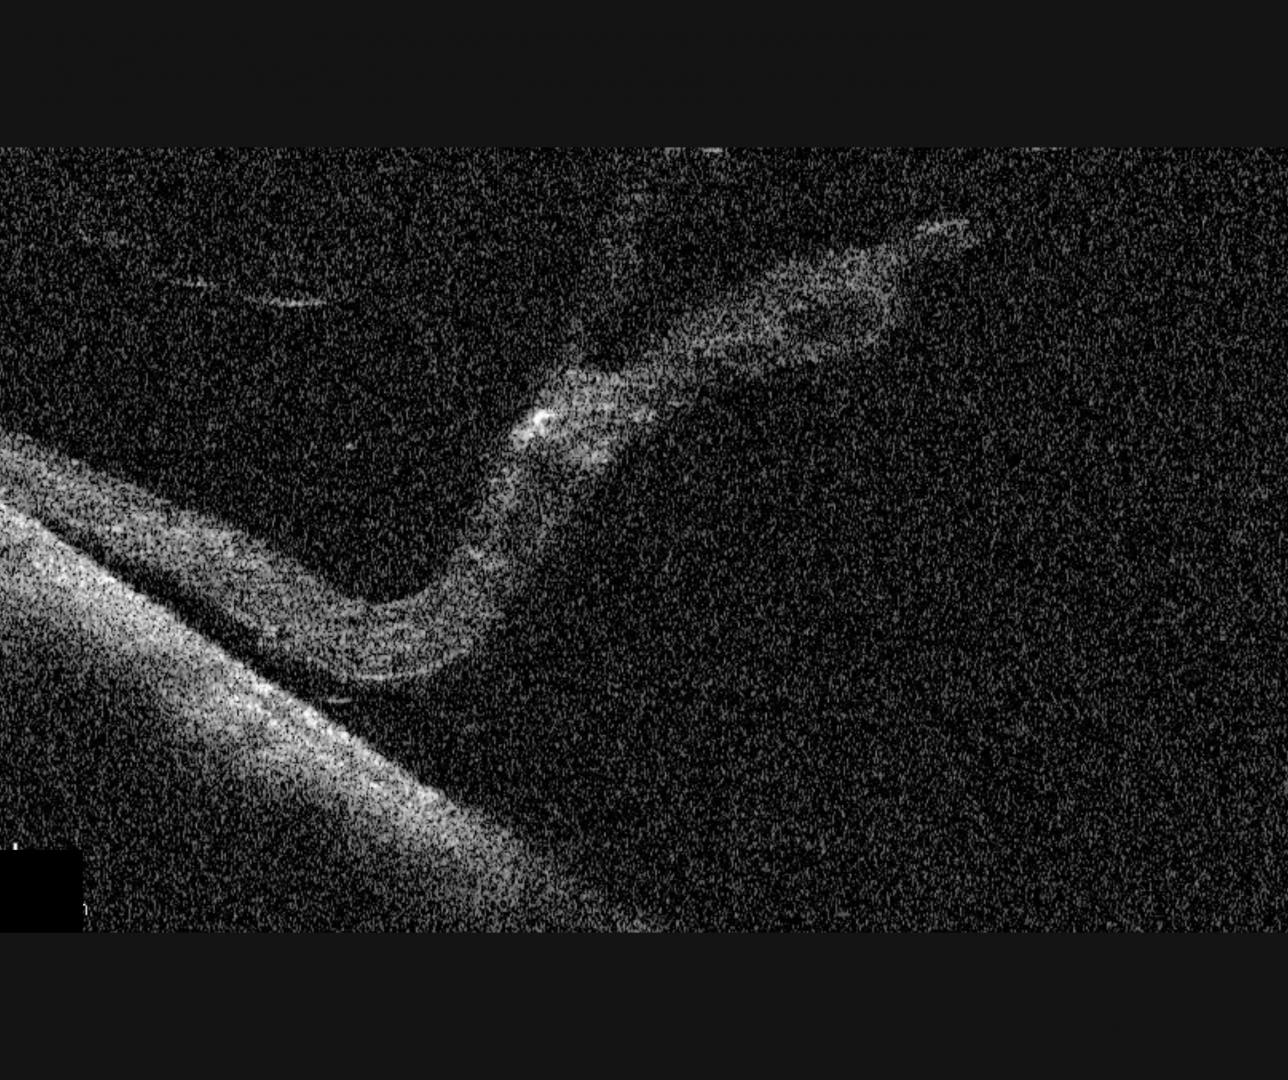

Spectralis OCT line scan through the edge of the detachment

More info